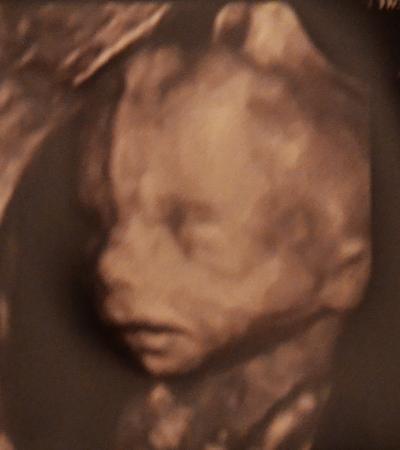

Hallo ihr Lieben, auch ich hatte gestern meien FA-Termin und meine 11-jährige Tochter durfte auch mit und war ganz begeistert von ihrem Mini-Brüderchen! Der kleine Mann hat sich auch von allen Seiten gezeigt und der Doc war hochzufrieden mit ihm. Messen konnte er ihn leider nicht, weil er ja ständig gezappelt hat, aber das Gewicht wurde auf ca. 350gr geschätzt (ganz ordentlich für die Woche!). Zunge rein, Zunge raus, Nabelschnurlimbo, Rolle vorwärts und rückwärts.......das ganze Programm! Nächste Woche habe ich noch das Organscreening beim Spezialisten und da gibt´s dann bestimmt noch mehr Fotos!

Bild zu Gesern beim FA (inkl. 4D-Bildchen) - Forum für Juni - Mamis

wow ist der hübsch!!! normalerweise sehen die in dieser woche noch so verschrumpelt aus in 3D und der kleine mann ist ja wirklich super hübsch! WOW